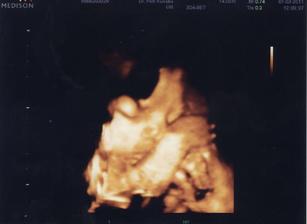

25.11. Na kontrole vše v pořádku. U ultrazvuku byl i budoucí tatínek a malý se náležitě předvedl. Vypadá to, že bude dělat Break dance 🙂 Má všechno, co mít má. Pan doktor nám sám od sebe ukázal i 3D UZ a vytiskl fotečku. Manžel sám od sebe jel nakoupit dětské oblečení a užíval si to málem více než já. Je krásné vidět, jak se na prcka těší. A viděli jsme camfrlika (výraz gynekologa) mezi nožkami 🙂